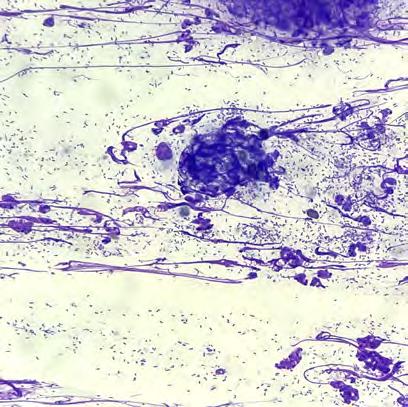

Bajo sedación con butorfanol (0,1 mg/kg IV Torphasol, aniMedica Senden-Bösensell, Alemania) y alfaxolona (5 mg/kg IV, Alfaxan Dechra, Uldum, Dinamarca) se le realizó una punción con aguja fina ecoguiada de bazo y linfonodo mesentérico caudal. La citología fue compatible con inflamación piogranulomatosa, sin observarse una causa subyacente.

El estudio histopatológico mostró una linfadenitis piogranulomatosa grave y generalizada; la totalidad de los fragmentos evaluados estaban ocupados por múltiples piogranulomas compuestos por centros de tejido necrótico y neutrófilos degenerados rodeados por abundantes macrófagos, células linfoplasmocitarias y fibroblastos reactivos. No se visualizaron microorganismos. La muestra fue positiva al RT-PCR (Real Time Polymerase Chain Reaction) del coronavirus entérico del hurón (FECV). El cultivo microbiológico resultó negativo. El diagnóstico de enfermedad por coronavirus sistémico del hurón (FSCVD) se confirmó mediante el análisis inmunohistoquímico frente al coronavirus felino del linfonodo mesentérico remitido. El anticuerpo utilizado presentaba positividad cruzada con el FSCV (Idexx laboratorios, Barcelona, España) (Fig. 2).

mesentérico 60 x. Tinción inmunohistoquímica. Numerosos macrófagos presentan inmunopositividad frente al anticuerpo con positividad cruzada con el coronavirus sistémico del hurón. Imagen cortesía de Laboratorios IDEXX.